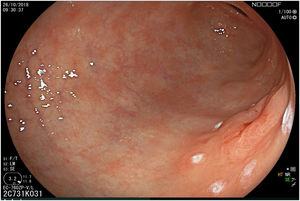

The endoscopic classification utilized to diagnose all lesions included in the present study was the Paris classification, whose validity is widely accepted by the different international consensuses and clinical guidelines. The following techniques were employed in the present study for the detection and characterization of the gastric lesions as follows: High-resolution white light endoscopy associated with a detailed and systematic review of the integrity of the gastric mucosa was initially utilized to identify lesions (Fig. 1). FICE (Flexible Spectral Imaging Colour Enhancement, Fujifilm Co., Japan) virtual chromoendoscopy or chromoendoscopy with 0.4% indigo carmine contrast staining were then employed to better characterize and delimit the lesions found (Fig. 2). In some cases, to optimize the evaluation of gastric abnormalities found (emphasizing special details, such as determining the microvascular pattern and specific alterations of the microsurface of the mucosa), minimum endoscopic image magnification, together with LCI (Linked Color Imaging, Fujifilm Co., Japan) and BLI (Blue Laser Imaging, Fujifilm Co., Japan) virtual chromoendoscopy, was utilized to show the demarcation line of the neoplastic lesion (Fig. 3), as well as microvascularization alterations (Fig. 4).